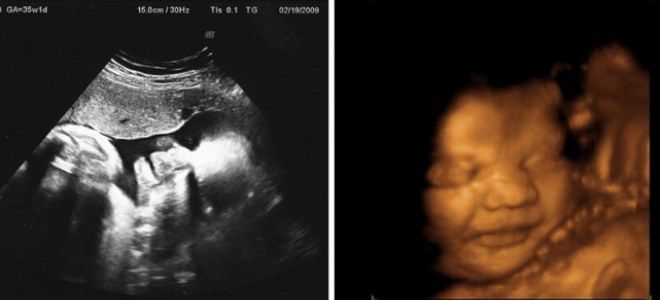

Как выглядит плод на 35 неделе беременности?

На 35-й неделе беременности внешний вид малыша практически не отличается от новорожденного. Главное отличие заключается в размерах отдельных частей тела. Лицо становится более округлым, приобретая типичные детские черты. Кожные складки на руках и ногах становятся более выраженными благодаря накоплению значительного количества подкожного жира.

Кожные покровы на этом этапе беременности полностью теряют красноватый оттенок и лануго – тонкие, прозрачные волоски, напоминающие легкий пух. Волосы начинают увеличиваться в длину, накапливая пигмент и приобретая характерный цвет. Первородная смазка исчезает с поверхности кожи, однако небольшие ее остатки все еще можно заметить на плечах и голове будущего малыша. Эта смазка поможет облегчить процесс прохождения ребенка через родовые пути.